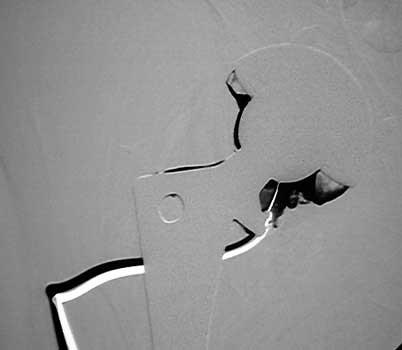

Arthrographic evidence of cup looseningcontrast enters

abnormally widened interface Gruen zone II and III